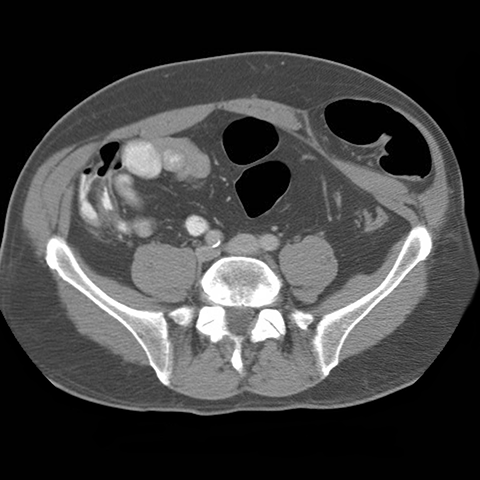

59 year-old male presents with an abdominal mass and pain. [5 of 5]